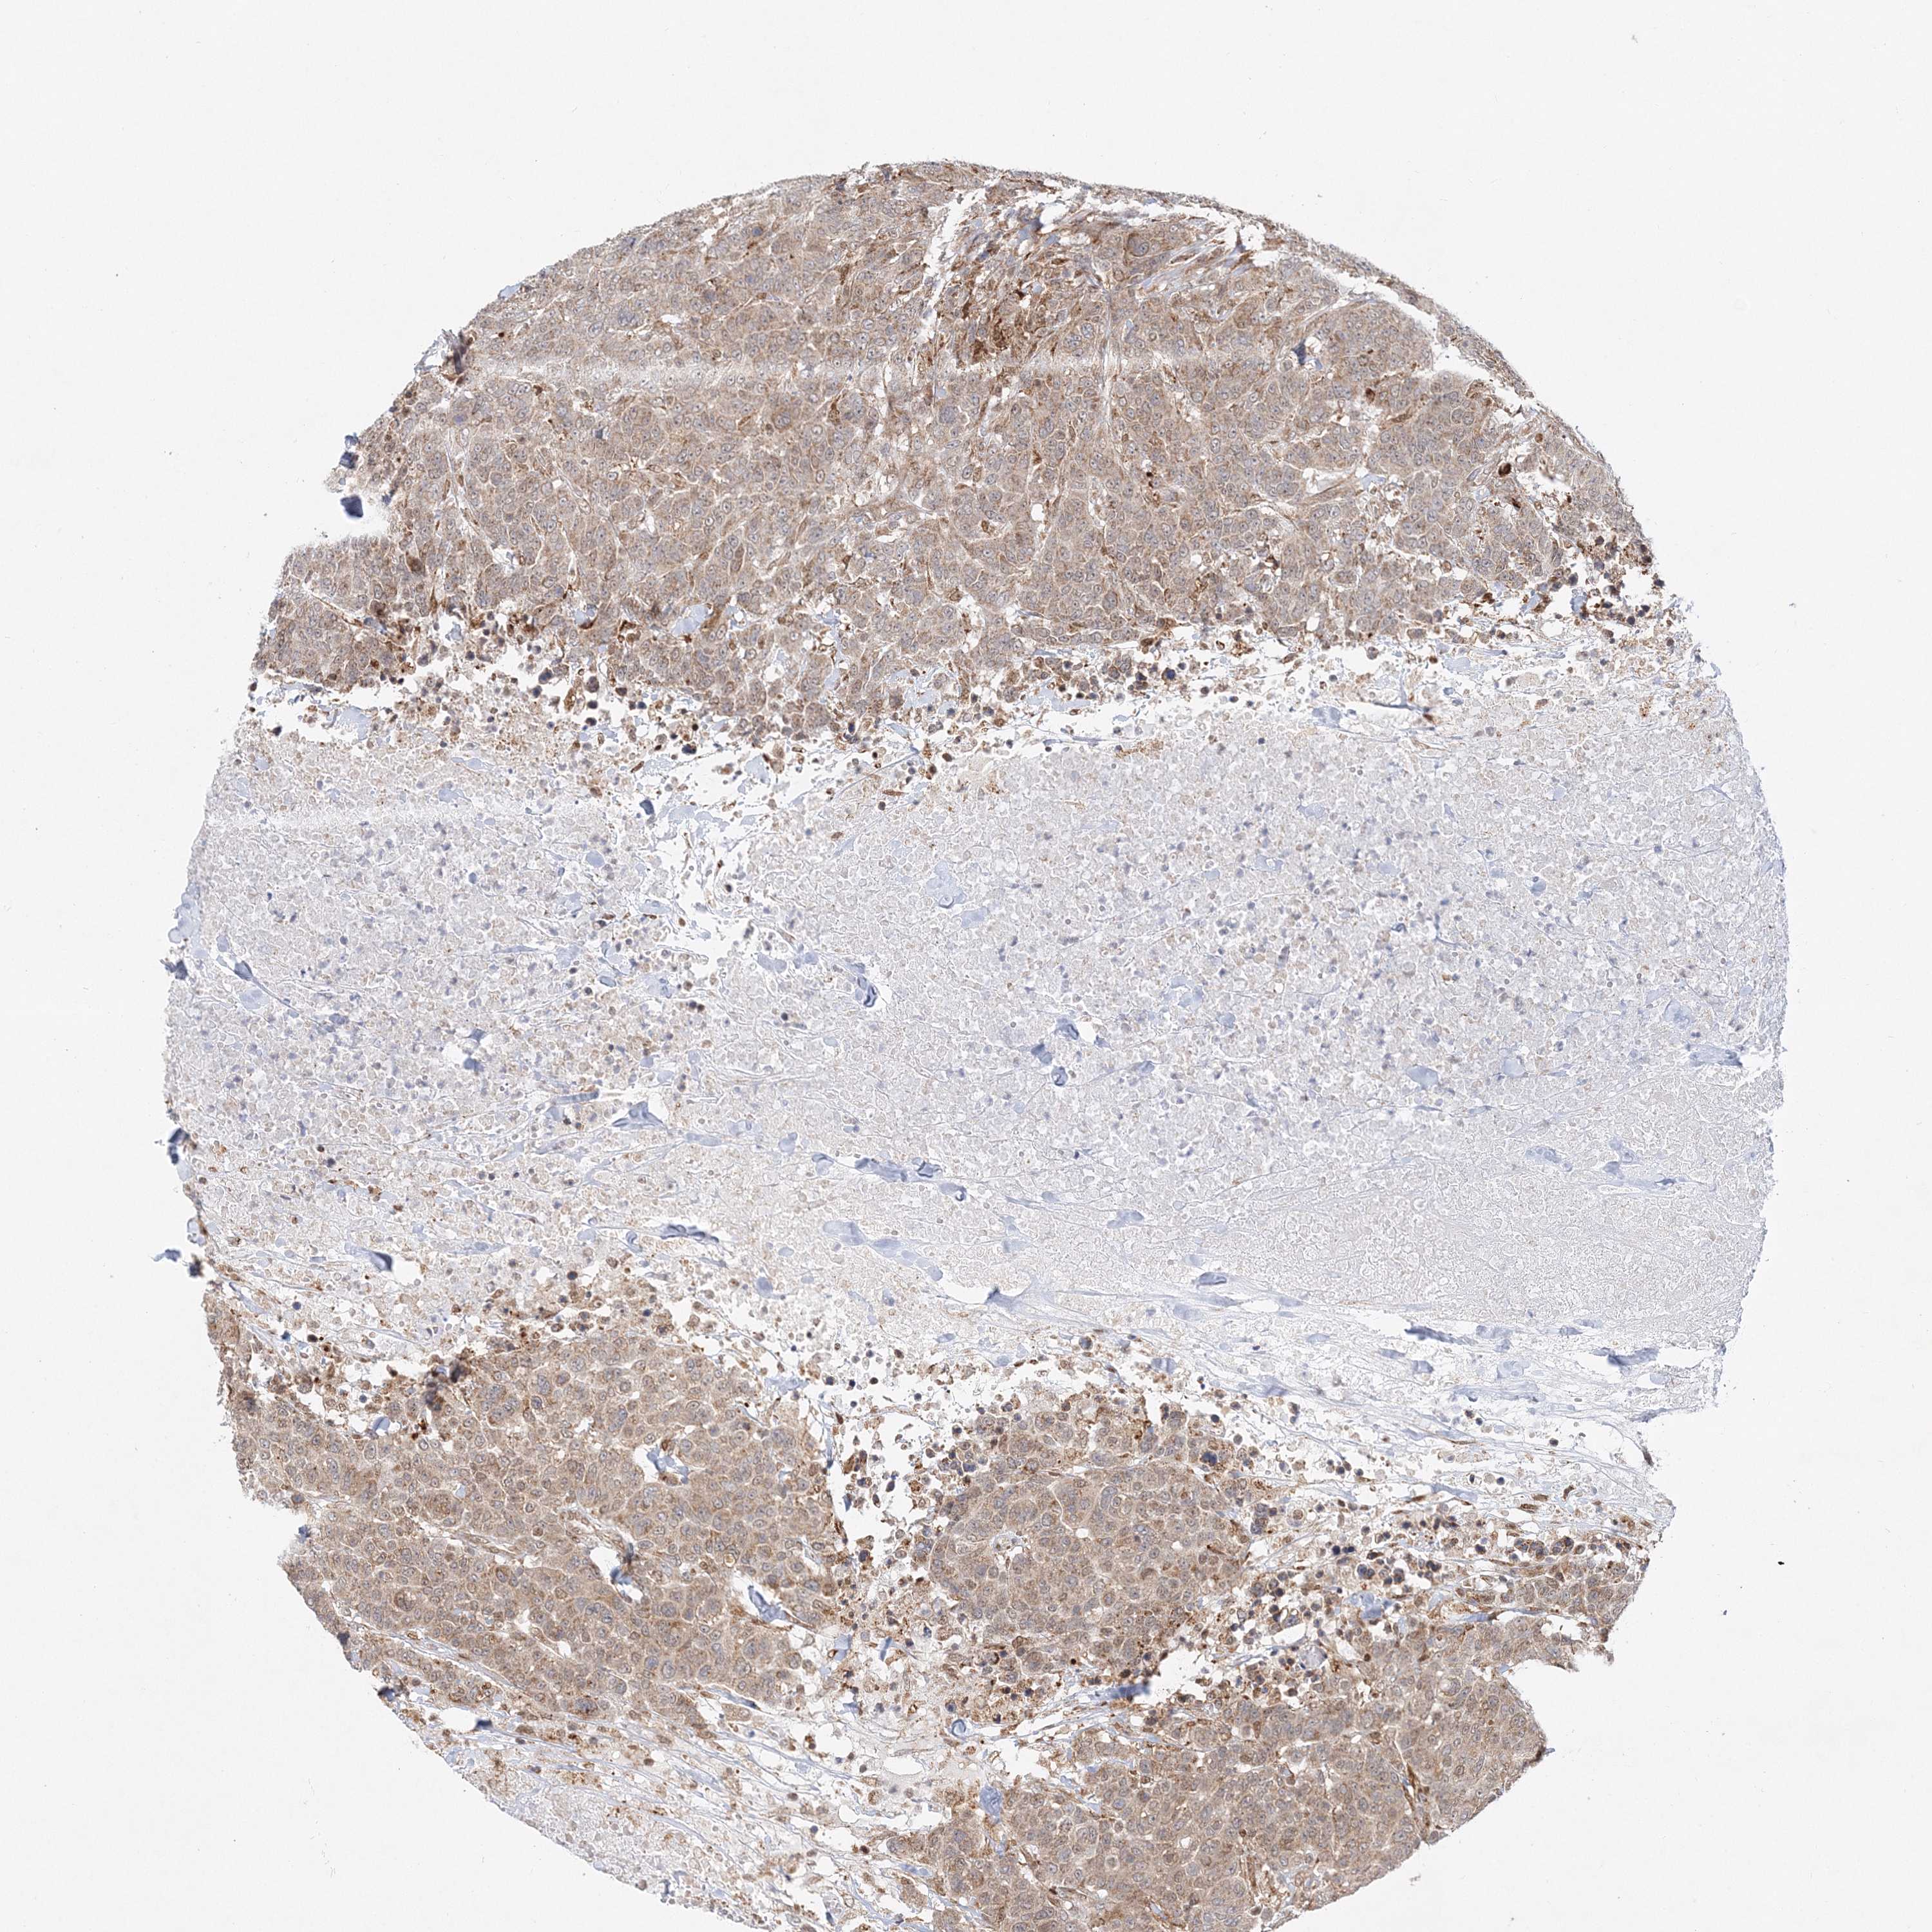

PATHOLOGY BREAST CANCER Show tissue menu

Breast cancer

Human pathology